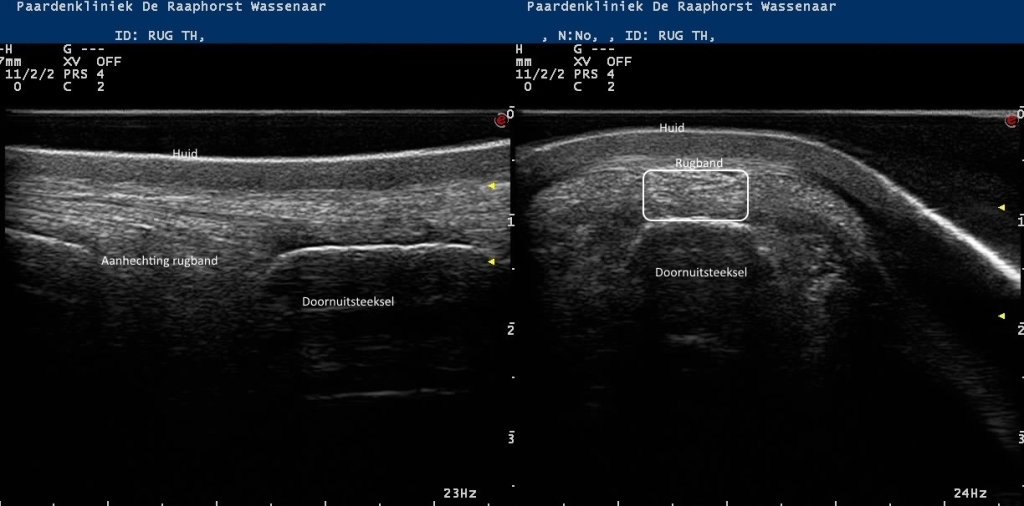

Rechts: Echobeeld van de rugband boven een doornuitsteeksel

Echobeeld van de rugband boven een doornuitsteeksel

Echobeelden van de lengte en dwarsdoorsnede van de rugband

Foto: Echobeelden van de lengte en dwarsdoorsnede van de rugband